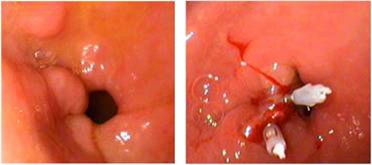

我院消化内科止血治疗又添新项目

消化道出血是消化科的常见病、多发病,也是消化科的急症之一。我院消化科经过多年学习、积累,目前已成功开展了:药物止血、内镜下药物喷洒止血术、内镜下药物注射止血术、三腔二囊管压迫止血术、内镜下药物热活检钳钳夹止血术、食管静脉曲张套扎术止血术,近期又开展了内镜下钛夹止血治疗术。经过临床实践证实:镜下止血术,对绝大多数消化道大出血的患者能够成功进行镜下止血。